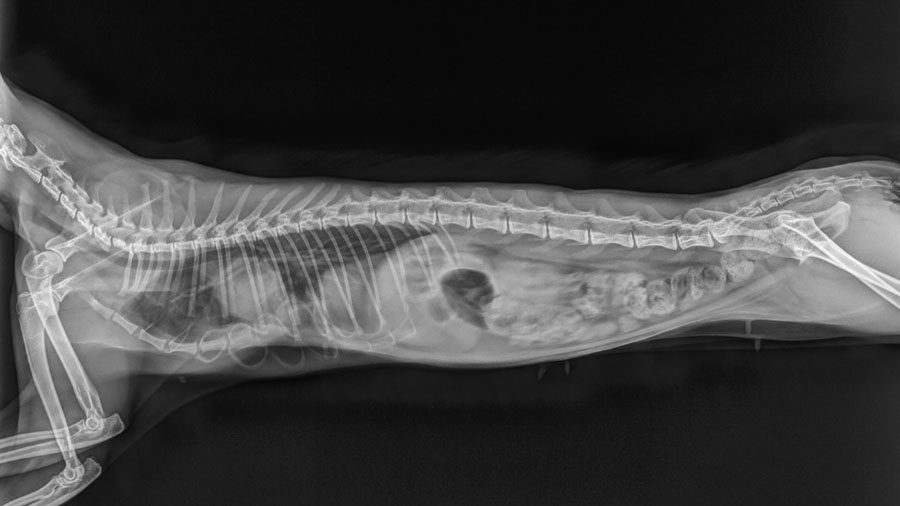

When I met the owners, they had simply come in seeking another temporary relief. But after examining the cat and reviewing the imaging— X-rays during inspiration and expiration showed just how dramatically the chest wall collapsed with every breath—I knew this wasn’t just a case for palliative care. It was a candidate, albeit a risky one, for surgical intervention.

Instead of trying to follow an existing formula, we built our plan around the cat’s unique anatomy. Using X-rays and video studies, I identified the "breakdown points" in the chest wall—the areas of maximum inward deviation and instability. I noted which costal cartilages were contributing to the deformity and which vertebral sternal segments were overly flexible or weak.

Our surgical plan was to remove the influence of the problematic ribs by severing their connection to the sternum. We would then reinforce the weakened sternal segments with a bent titanium reconstruction plate, designed to mimic the natural contour of a healthy sternum. It wasn’t a fancy, custom 3D-printed solution—we don’t have that capability here—but it would be strong enough and adaptable enough to offer real structural support.

Over the next 10 days, we kept the cat hospitalized, providing antibiotics, anti-inflammatory medications, and close observation. There were no signs of infection, no implant rejection, no respiratory distress. Follow-up X-rays over the next few months confirmed that the plate remained intact, and the chest structure was stable. Even better, the cat gained 50% of its body weight in three months, a sign not just of recovery but of thriving.